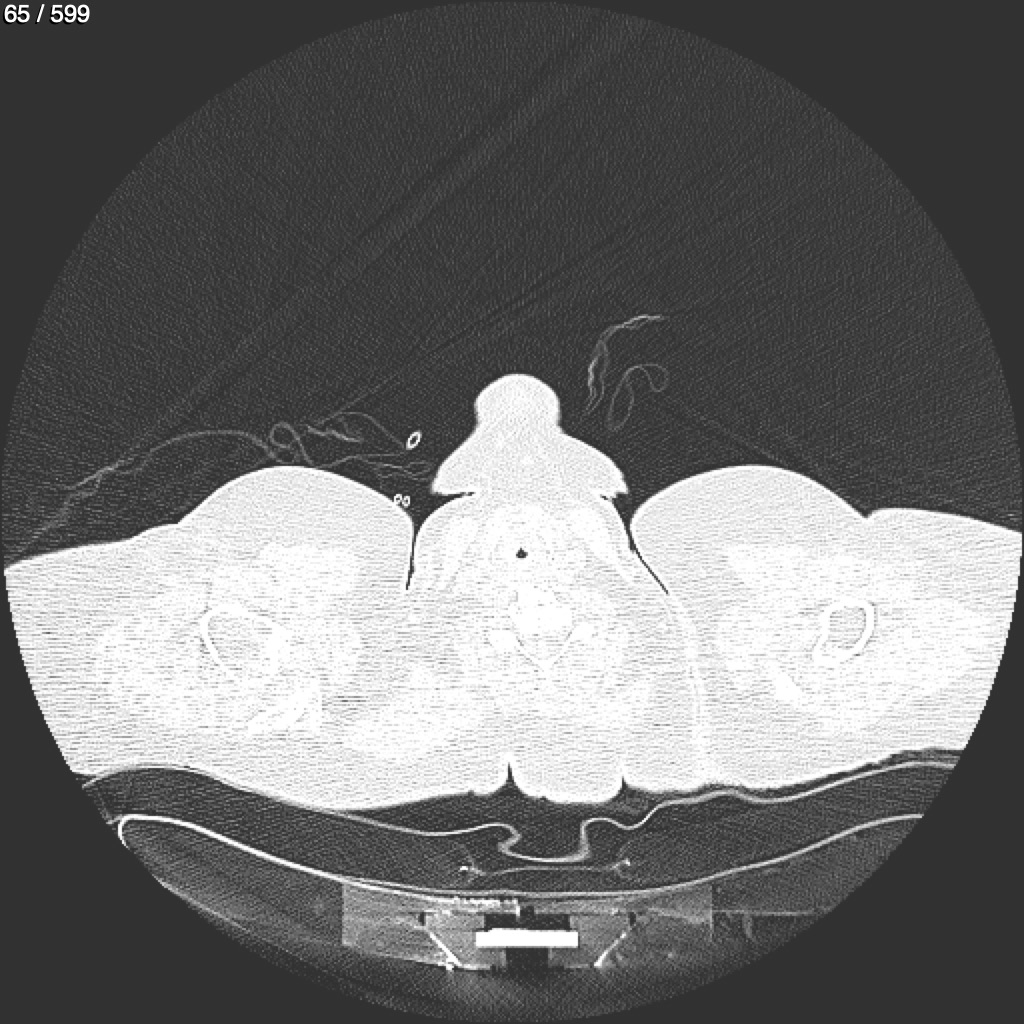

Home G​l​o​r​i​a​ ​G​l​a​d​y​s​ ​B​e​a​s​l​e​y​ ​-​ ​T​ó​r​a​x​ ​T​o​r​a​x​_​S​i​m​p​l​e​ ​(​A​d​u​l​t​o​)